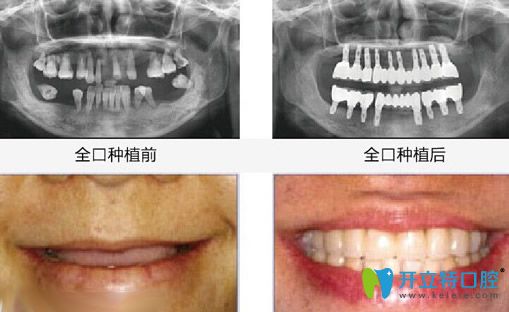

【全口牙缺失種植效果】

湛江致美口腔全口牙種植牙案例效果

種植牙前:全口牙齒缺失;

種植牙顧客評(píng)價(jià):由于牙齒掉光了,平時(shí)只能吃些稀飯和面條之類的食物,所以身體也不如以前好了,在女兒的帶領(lǐng)下到湛江致美做了全口牙種植牙,沒想到當(dāng)天回家就能吃東西,而且看著也和真牙沒什么兩樣!